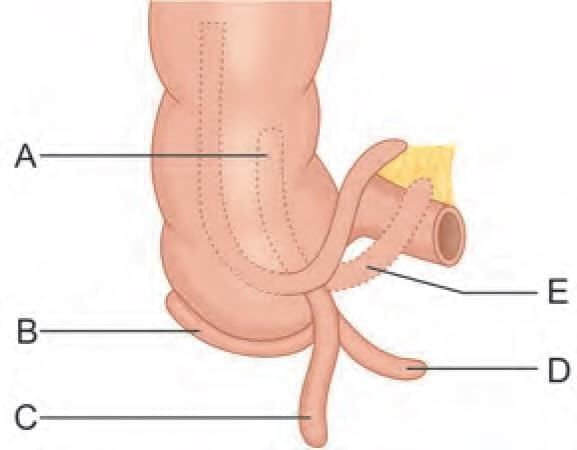

Match the location of vermiform appendix with the labelling given in the diagram: (INI-CET May 2023)